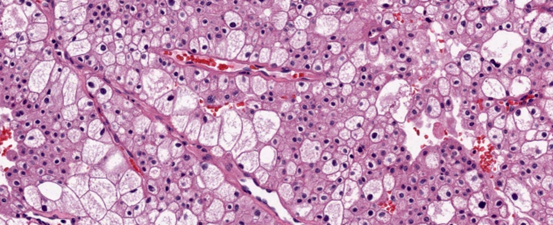

Ung thư biểu mô tế bào thận tế bào sáng (70-80%)

Đại thể

Thường là khối u vỏ thận một bên và đơn ổ, kích thước trung bình khoảng 7 cm. Khối u thường có ranh giới rõ, được bao quanh bởi giả bao u, phát triển theo kiểu đẩy nở và lồi ra từ vỏ thận. Hình thái đại thể đa dạng với thành phần đặc và nang, kèm các vùng xơ hóa màu xám và các ổ xuất huyết mới hoặc cũ màu nâu; hoại tử và biến đổi nang gặp thường xuyên. Khối u có màu vàng ánh kim do hàm lượng lipid cao; các khối u có độ mô học cao hơn có thể không có màu vàng do hàm lượng lipid và glycogen thấp hơn. Các vùng mềm, dạng thịt có thể phản ánh sự hiện diện của biệt hóa dạng sarcomatoid. Thường xuyên ghi nhận xâm lấn tĩnh mạch thận và xoang thận. Tổn thương hai bên và đa ổ là đặc điểm gợi ý bệnh lý di truyền.

Vi thể

Thường gặp các đám và bè tế bào sắp xếp chặt chẽ, tế bào có bào tương sáng và màng tế bào rõ. Bào tương hạt bắt màu eosin có thể được quan sát trong các khối u độ mô học cao hoặc ở vùng lân cận các ổ xuất huyết hay hoại tử. Hệ thống các mạch máu nhỏ, thành mỏng, phân nhánh dạng cây là một đặc điểm chẩn đoán quan trọng, đặc biệt trong các trường hợp có bào tương hạt eosin. Các kiểu cấu trúc kiến trúc gồm dạng đặc, dạng phế nang hay dạng ổ (alveolar hoặc nested), dạng tuyến nang hay ống (acinar hoặc tubular), dạng vi nang chứa hồng cầu thoát mạch hoặc dịch ái toan, và đôi khi dạng đại nang. Có thể gặp cấu trúc nhú khu trú, tuy nhiên sự hình thành nhú nổi bật làm tăng khả năng các phân nhóm khác như u thận tế bào sáng dạng nhú, ung thư biểu mô tế bào thận có tái sắp xếp TFE3, biến đổi TFEB hoặc đột biến ELOC. Mô đệm thường không đặc hiệu, không có phản ứng xơ sinh, trái ngược với ung thư biểu mô ống góp hoặc ung thư biểu mô niệu mạc, và chỉ có đáp ứng viêm tối thiểu. Các đặc điểm độ mô học cao bao gồm biệt hóa dạng rhabdoid với các tế bào ác tính lớn, độ ác tính cao, bào tương eosin đồng nhất phong phú, nhân lệch tâm và các thể vùi eosin hình cầu trong bào tương, cũng như biệt hóa dạng sarcomatoid, có thể xảy ra ở bất kỳ phân nhóm ung thư biểu mô tế bào thận nào. Hoại tử khối u là một đặc điểm có thể gặp. Các biến thể mô học ít gặp, hiện chưa rõ ý nghĩa tiên lượng, bao gồm dạng nang, dạng giả nhú, tạo xương lạc chỗ, các thể cầu hyaline trong và ngoài tế bào, các thể vùi bào tương bắt màu kiềm, sự hiện diện phong phú của tế bào khổng lồ đa nhân, các u hạt dạng sarcoid hoặc hình ảnh myospherulosis. Ung thư biểu mô tế bào thận tế bào sáng có đột biến BAP1 thường biểu hiện cấu trúc nhú, bào tương eosin và các thể cầu trong bào tương. Trên thực hành, các vùng u độ mô học thấp hơn với hình thái điển hình của ung thư biểu mô tế bào thận tế bào sáng là những vùng hữu ích nhất cho chẩn đoán, trong khi các khối u độ mô học cao hơn có thể biểu hiện các đặc điểm chồng lấp với các тип ung thư biểu mô tế bào thận khác.

Hình 5. ccRCC với hệ thống mạch xoang dạng cây phân nhánh, thành mạch mỏng

Hình 6. ccRCC, có biến đổi vi nang và đại nang, kèm hiện tượng thoát hồng cầu